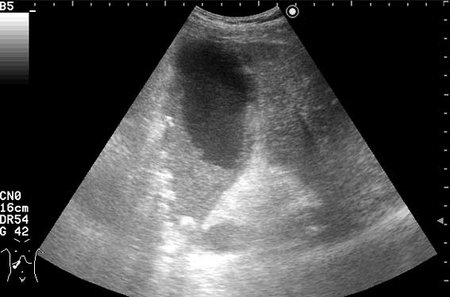

УЗИ: Острый гангренозный холецистит

Мужчина с болями вправом подреберье и температурой.

ЖКБ. Острый гангренозный холецистит?